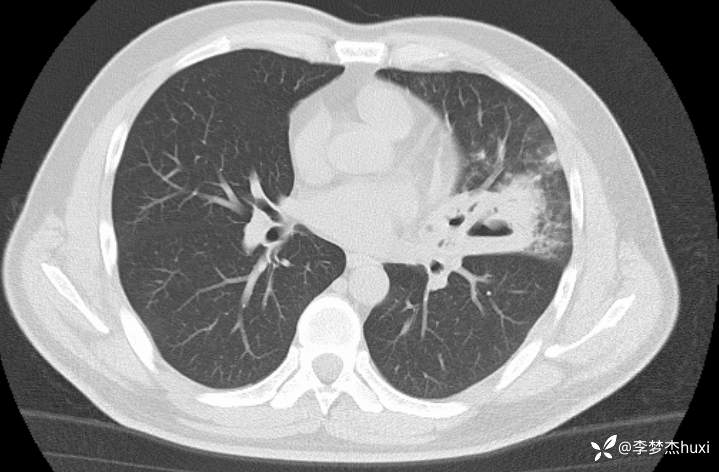

男性40岁,咳嗽、咳痰5天,CT示空洞病变,可能是啥病原菌?

【现病史及既往史】: 1.患者中年 男,患者缘于5天前前无诱因出现咳嗽、咳痰,为黄痰,伴臭味,痰不易咳出,伴发热,最高体温不详,无喘息、憋气,无胸痛,无咯血,无腹痛腹泻,无恶心、呕吐。院外未应用药物治疗,症状无明显好转,为求进一步治疗来院就诊,门诊查胸部CT;双肺炎症,左肺上叶厚壁空洞形成,双肺纹理增重,双侧胸膜局限性增厚,脂肪肝,建议结合临床复查。以“肺炎”收住院;。

【临床诊断】:肺脓肿伴有肺炎。